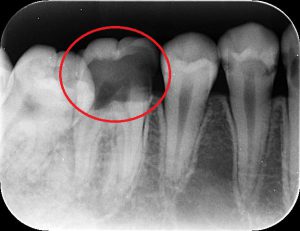

こちらをご覧ください。

こちらは歯のレントゲン写真になります。印があるところ、黒く透けていますよね?そこが虫歯です。

そしてその下に細い管のようなものがあります。その管の中にある黒い線は、歯の神経です。

虫歯が大きくなりすぎて歯の神経の部屋に近づいていますね。

こういう場合は歯の神経に虫歯の菌が感染して強い痛みが出てくるので神経を取る治療をしたほうがいいです。